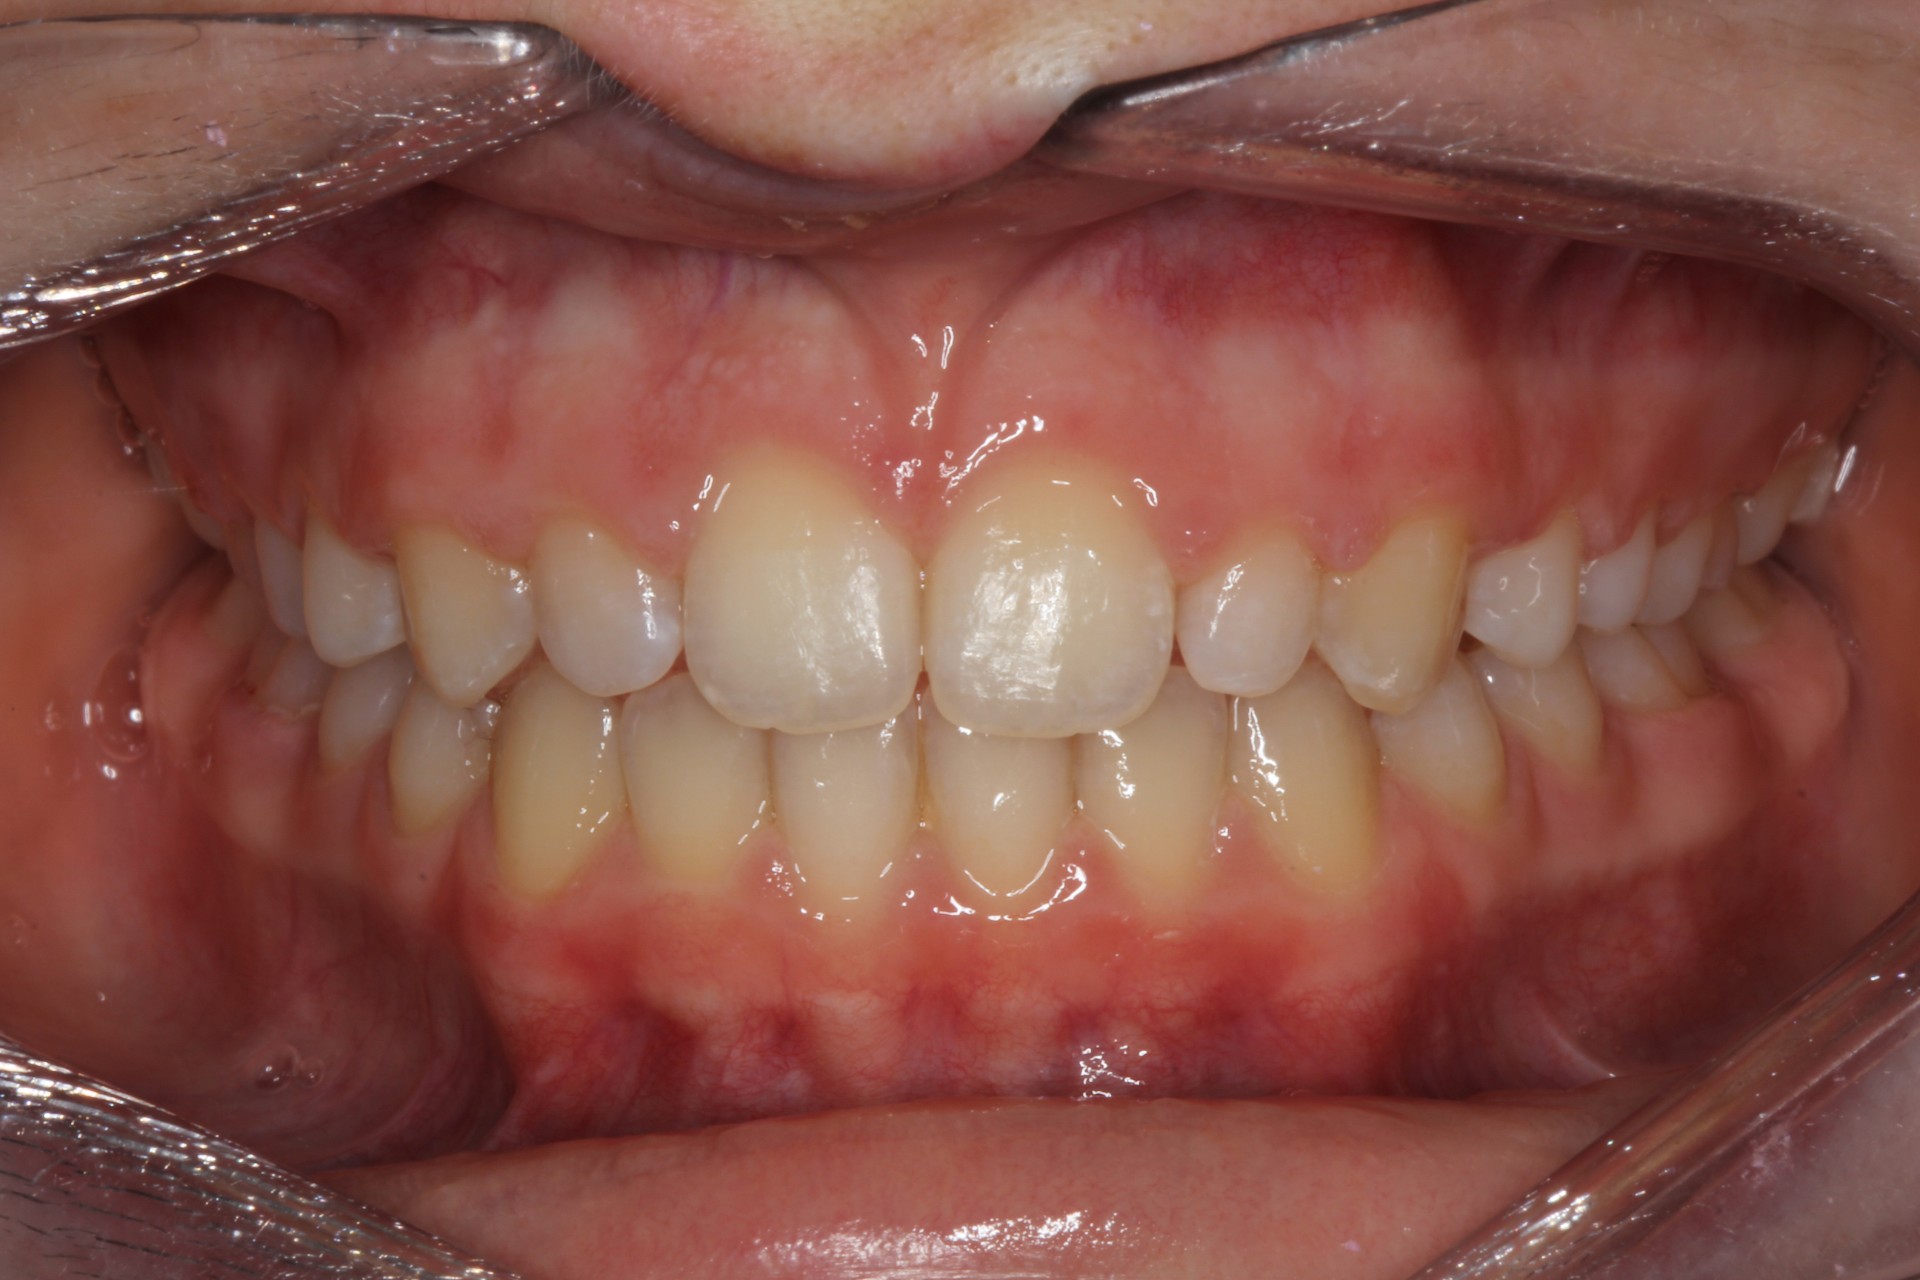

Protruding front teeth with midline diastema – Child case